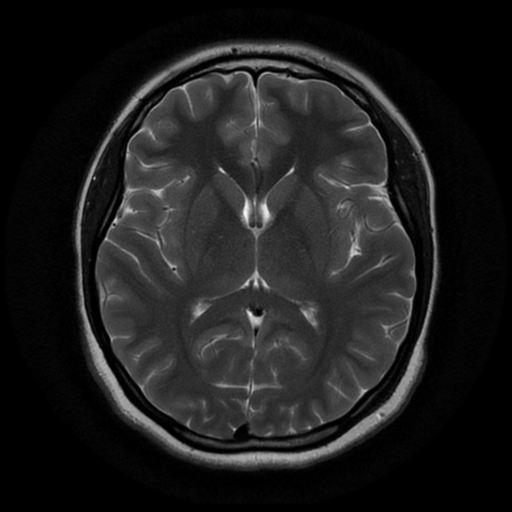

MRI

MRI